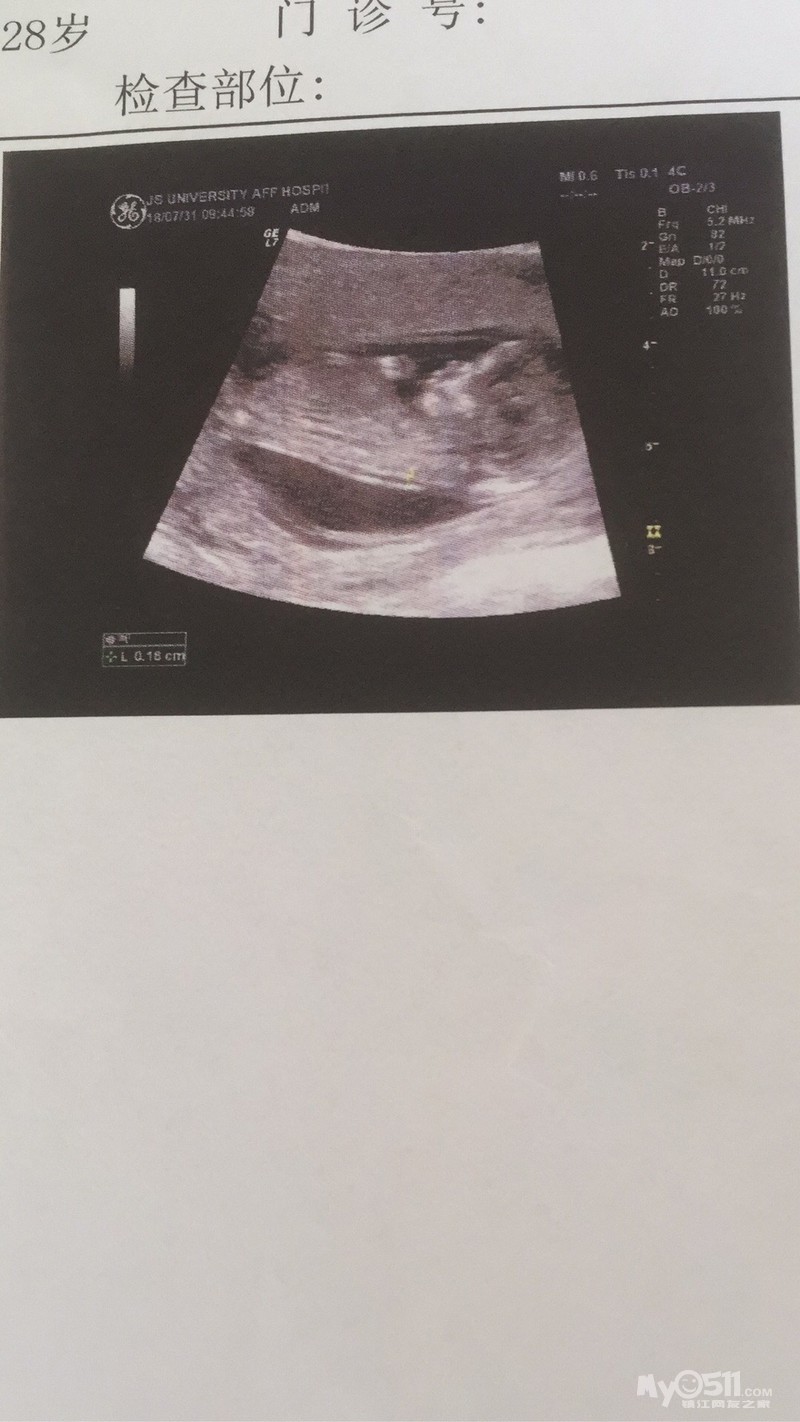

生产医院:江滨医院

我的好孕故事:虽然计划了你的到来!但是去医院确定你真的到来的时候!我和爸爸还是很兴奋很意外!没曾想过你到来的如此之快!虽然你的到来让我难受到只能躺床上!吃不下睡不好但是还是很感谢你选择我做妈妈!我和爸爸准备着你要出生的东西!很幸福!时间过的也很快!还有两个多月你就要来啦